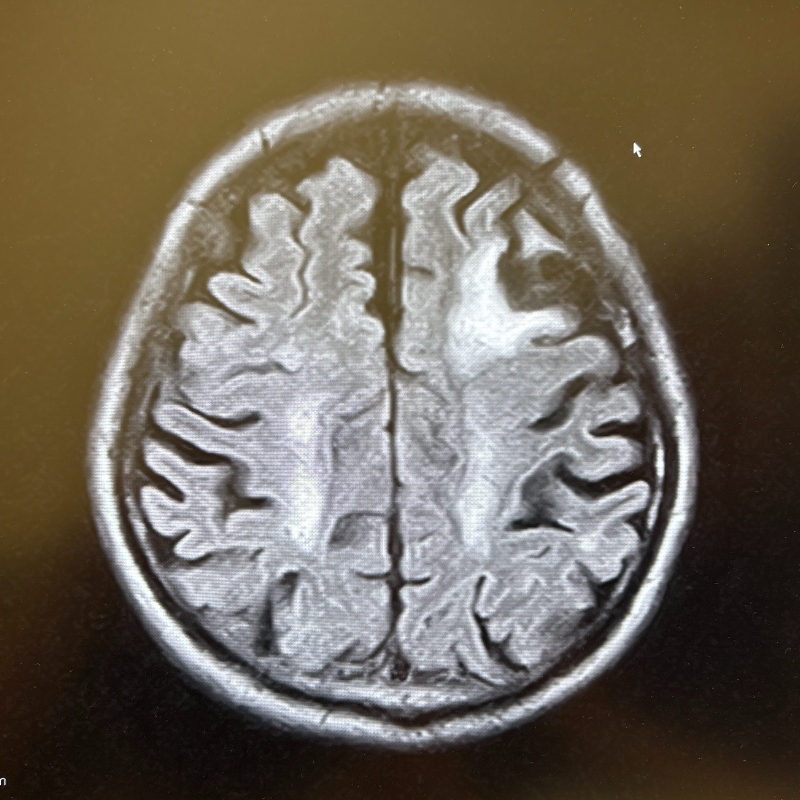

MRI画像例

下の画像は、当院で行うMRI・MRA検査で撮影できる脳の写真の一例です。

MRIでは脳の形や組織の状態を、MRAでは脳の血管の様子を詳しく確認できます。

2D画像